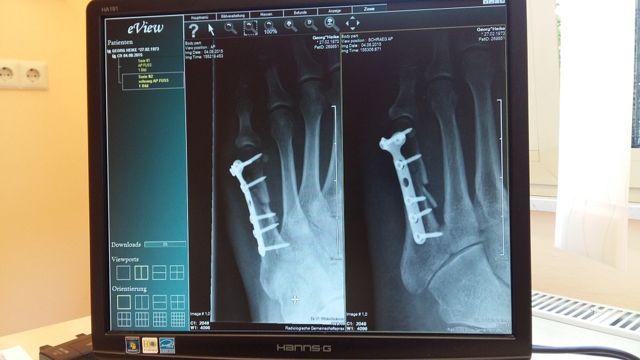

Напомним, сегодня в составе госпиталя работает поликлиника, диагностические отделения, стационар, операционный блок, отделение реабилитации с тренажерами и ваннами и другие подразделения.